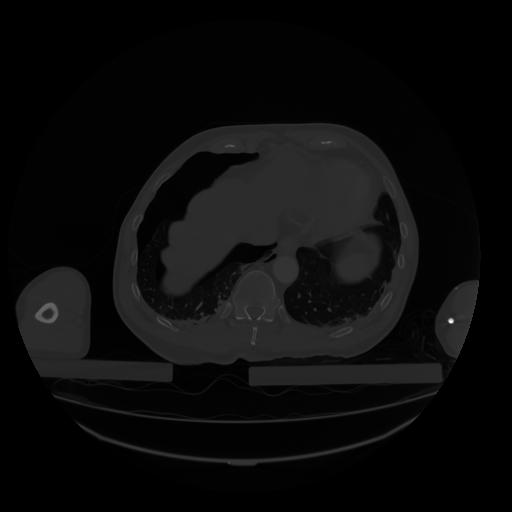

28 CUERPO,CE,Vol,2.0,CUERPO,,